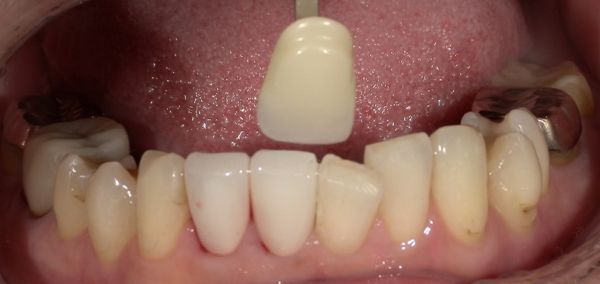

まず、除去および形成を行い、仮歯を仮着しました。

型取り、色合わせのための写真撮影を行い最終補綴へ移行しました。

色調に関しては、写真を多数撮影して、提携ラボ歯科技工士さんへお送りし、色調の再現をお願いしております。

使用カメラに関しても技工士と同じものを使用する事で、色の誤差などを最小限に減らすよう工夫しております。